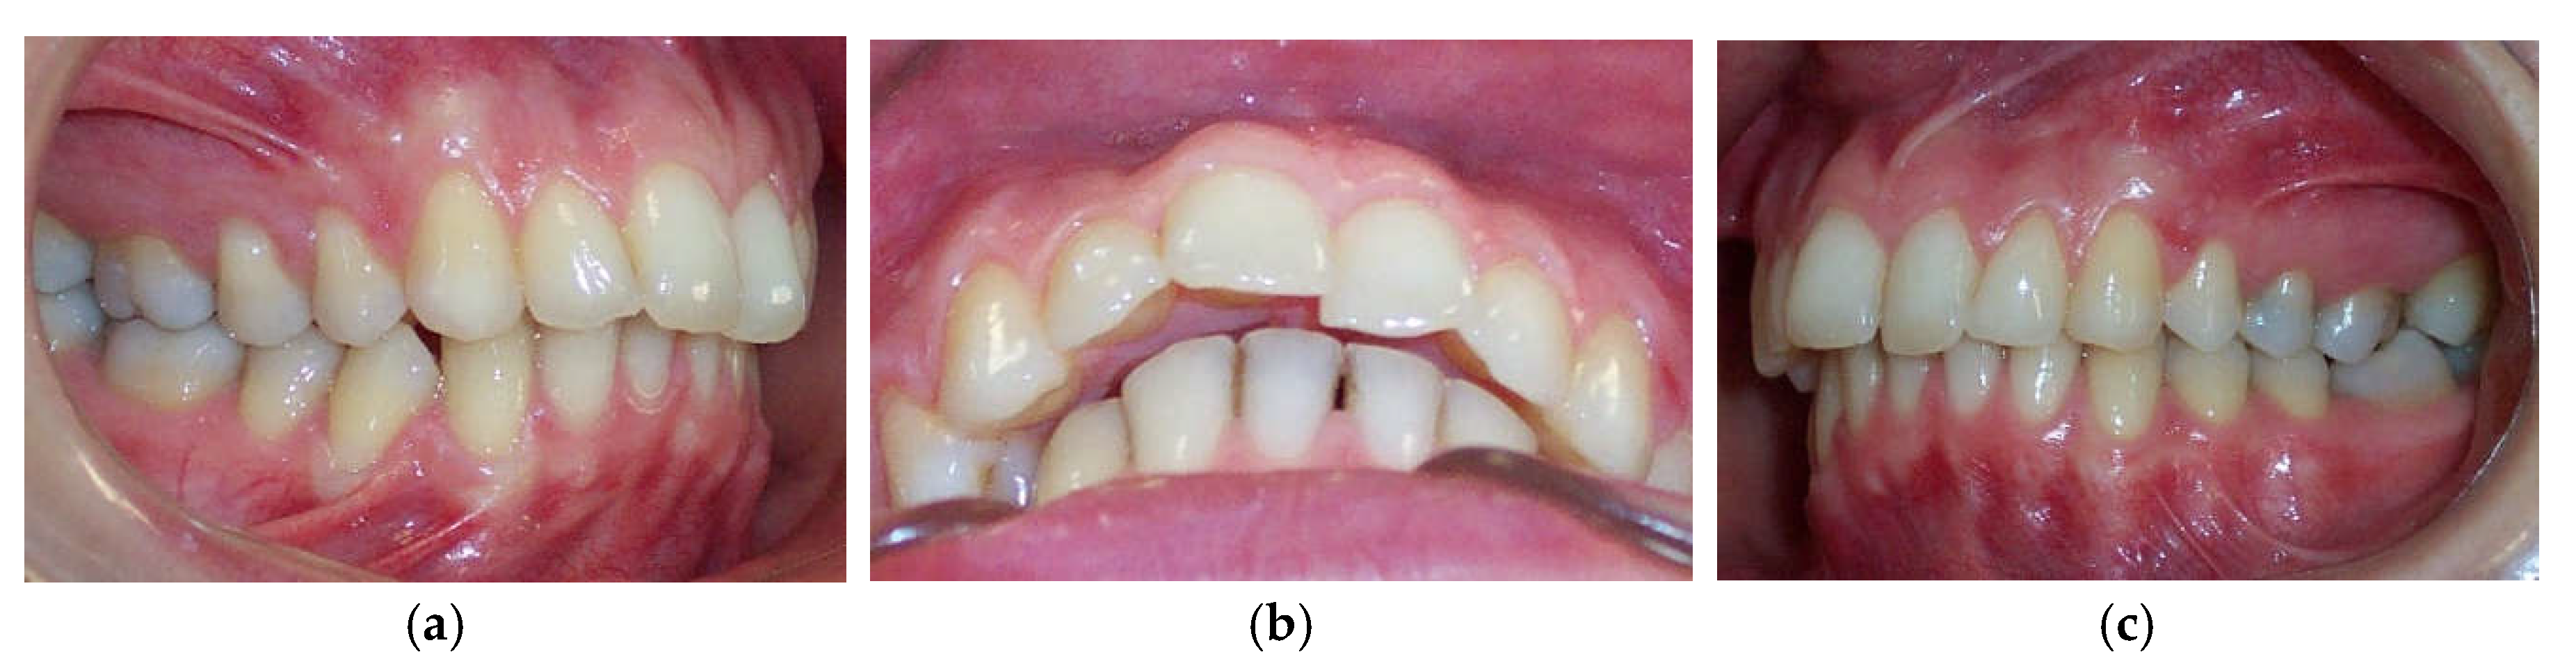

According to Spearman’s correlation, test results of the anamnestic and diagnostic criteria of RDC/TMD were strongly positively correlated (p < 0.05) with the condylar displacements in the vertical and transverse planes before the splint therapy. When compared before and after, interarch relationship changes were observed intraorally and from models mounted on a semi-adjustable articulator after the neuromuscular deprogramming (Figure 5).

The significant reduction in condylar displacement and the achievement of an orthopedically stable musculoskeletal position following the splint therapy directly correlated with the improvement in TMD symptomatology. Hence, the pain related to the area of the temporomandibular joint and masticatory muscles reported by 55% of patients before the splint therapy was completely eliminated after the splint therapy, and this result was the same for the intermittent jaw locking. Following the splint therapy, headache symptoms were reduced for more than 90% of patients, corresponding with the study findings of Kemper and Okeson [44]. After the splint therapy, jaw clicking was reduced for more than 80% of patients. Clinical findings regarding the signs of tenderness on palpation in the masticatory muscles, lateral pole, temporalis tendon, and posterior attachment inside the ear showed a statistically significant reduction in signs after the splint therapy. Crawford reported a significant increase in the signs and symptoms of TMD as the condylar displacement in vertical and horizontal planes was raised from 1 to 2 mm [12]. He et al. demonstrated that 72.9% of pre-treated orthodontic patients with signs and symptoms of TMD had a condylar displacement greater than 1 mm in the vertical and horizontal and 0.5 mm in the transverse plane, while only 11.4% of asymptomatic patients in the control group had increased condylar displacement. They then concluded that the condylar displacements identified in symptomatic patients were a significant contributory factor to the development of signs and symptoms of TMD [15]. This study found that the significant reduction in condylar displacement obtained via the splint therapy directly correlated with the improvement or elimination of signs and symptoms of TMD, concurring with the findings of similar investigations [7,12,22,23,24,29]. Moreover, our results agreed with those of authors who found a positive correlation between therapy with an occlusal splint constructed in the CR position and improvement in TMD symptomatology, albeit that in these investigations, CPI evaluation was not used [45,46,47,48,49]. Furthermore, a significant increase in condylar displacement between the CR and MI generates changes in the dental relationship that can be observed intraorally in the CR position and from dental casts mounted in the CR. Changes in dental interarch characteristics that occur following deprogramming of the neuromuscular system are presented in Figure 7 and Figure 8.

Figure 7. Intraoral view of occlusion in the MI before splint therapy: (a) Right lateral view; (b) Inferior overjet view; (c) Left lateral view. Intraoral view of occlusion in the CR following splint therapy: (d) Right lateral view; (e) Inferior overjet view; (f) Left lateral view. The magnitude of horizontal (overjet) interarch discrepancy increased and Class II malocclusion was more pronounced. The magnitude of vertical (overbite) interarch discrepancy decreased and lower facial height increased.